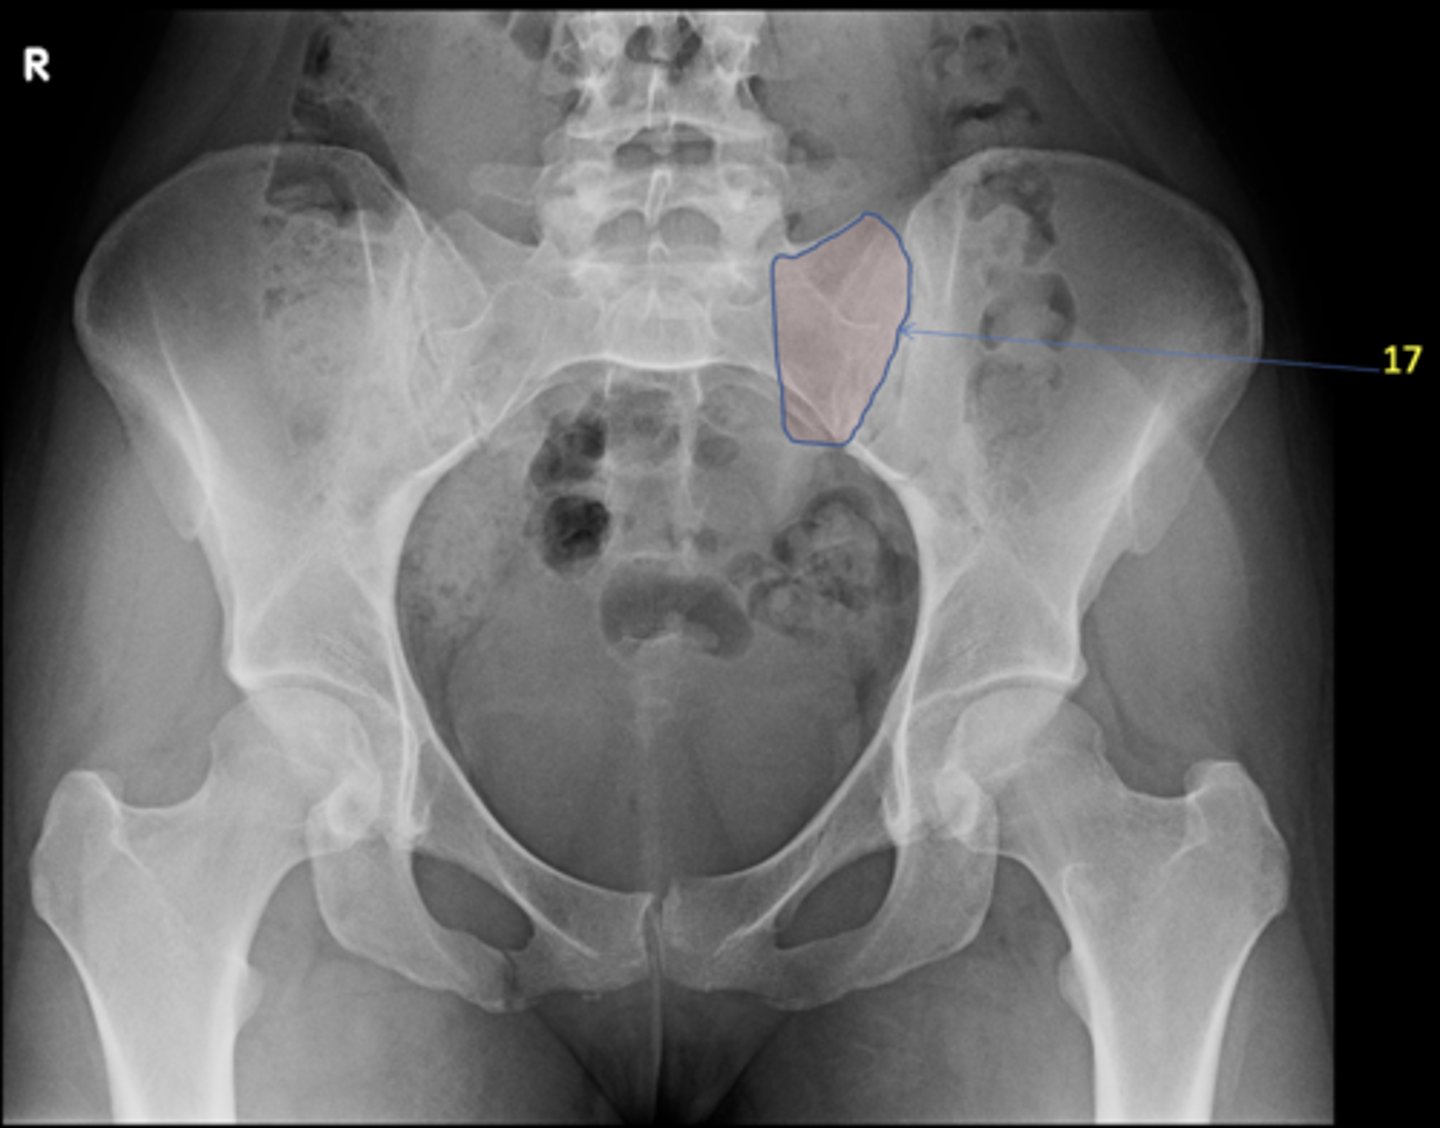

16

New cards

Left sacral ala

ID 17

<p>ID 17</p>

17

Right femoral head

ID 19

<p>ID 19</p>